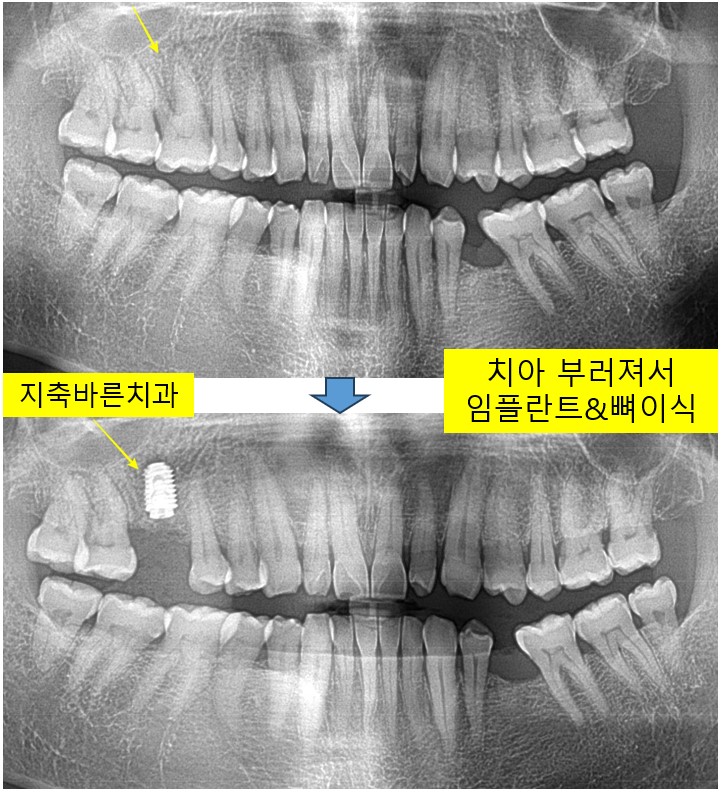

<치아가 부러져서 염증 - 발치 후 임플란트>지축치과 지축역치과 삼송치과 원흥치과 원당치과 구파발치과 불광치과 종로치과 서대문치과 마두치과 대화치과 파주치과 금촌치과 양주치과 미백

오른쪽 위 잇몸이 한달전부터 아프시다면서, 2024년 9월 50대 Lㅁㅁ 님께서 내원해주셨습니다. 1. 검진을 ...